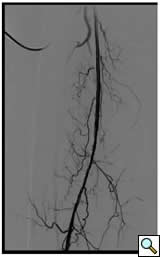

Case 3: An 81-year-old male with rest pain. The patient underwent angiography via an antegrade approach, which revealed extensive

![]() |

| Figure 3A |

| Figure 3B |

| Figure 3C |

calcific lesions of the superficial femoral artery (Figure 3A) and a lesion in the tibio-peroneal trunk (Figure 3B). The SFA lesions were debulked with a laser and the patency restored with Viabahn stents (Figure 3C). The tibio-peroneal represented the sole run off and was left as we were worried about creating a disaster if the lesion ruptured or dissected. ABI increase from 0.19 pre-procedure to 0.55 post and the patient is now able to ambulate with manageable claudication. Options to treat the more distal lesion could involve using a distal protection device and coronary balloons and/or stents.